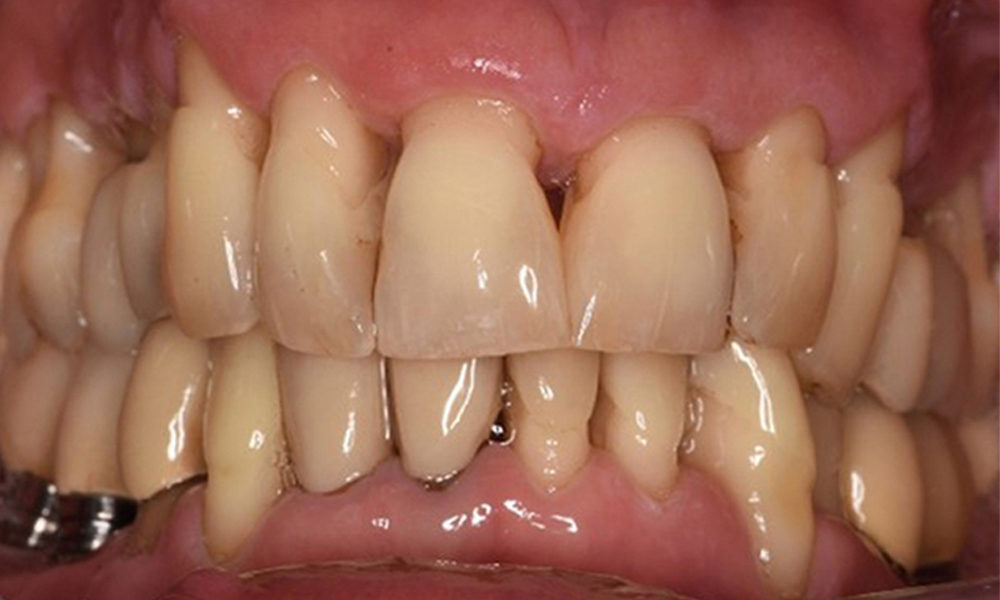

Front view of dentition (upper and lower jaw)

Front view

Oral hygiene and patient compliance are very good (see picture “front view”). All that is required is repeat instruction and motivation to maintain oral hygiene behaviour.